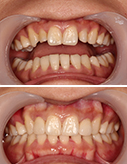

“牙缝大”不开心-瓷贴面7天让你美丽无忧

15岁小帅哥全口虫牙 根管修复露笑颜

不要等牙疼时才想起保护

龋齿不可大意 牙髓炎太可怕

治疗牙周病 还得早着手

只想变美 那就现在

健康爱美的大门前没有“男士止步”

收拾小龅牙 最正确的决定

小小种植牙 托起大梦想

种牙种健康 最美夕阳红